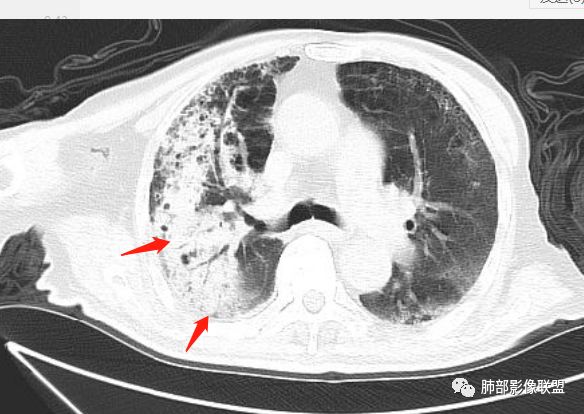

王秀仙:

右肺上叶大片实变,其内可见虫蚀样空洞及扩张支气管,其中一空洞内可见曲菌球样结构,右肺体积略缩小。老年糖尿病患者,慢阻肺背景,考虑右肺上叶干酪性肺炎并曲霉感染。

闫美利:

老年男性,糖尿病患者,右上肺大片实变,内可见多发虫蚀样空洞,右尖段近胸膜处一空洞内可见一类圆形结节影,支气管扩张,淋巴结肿大,双下肺索条,胸膜增厚。结合糖尿病病史,首选考虑结核干酪性肺炎合并曲霉菌感染,待排肺炎型肺癌

双胞胎的结核与粘液腺癌

粘液腺癌和干酪性肺炎鉴别:

1、结核干酪空洞常很干净,很彻底,而粘液腺癌空洞内有液性成份,不干净。

2、支气管:干酪样肺炎内的支气管破坏的,扩张的,粘液腺癌小支气管多狭窄的堵塞的,大支气管较完好,枯枝征。

3、增强扫描很重要,增强后,结核的坏死很彻底,很少异常强化,(鳞癌也类同)。而粘液腺癌血管常显影,有时是毛糙的,整体密度偏低,哟其实纵膈窗。

4、症状,粘液腺癌白痰为主。

5、这样的结核灶,其实痰检出抗酸杆菌阳性的几率常较大。

6、结核灶周围磨玻璃少见,粘液腺癌磨玻璃影清楚。结核灶常有收缩,钙化,树丫等等。很重要,粘液腺癌分布弥漫,远处飘散的边界清楚的磨玻璃结节影有重要诊断意义。

7、形态,结核收缩,粘液腺癌局部膨胀,叶间裂有时候是膨胀下坠的。

粘液腺癌的很少见纵隔淋巴结肿大,而其他腺癌常见。

如果胸膜下有间隙,不支持肺炎型肺癌